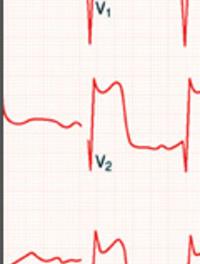

Les essais cliniques randomisés ont bien montré que la resynchronisation cardiaque améliorait significativement la qualité de vie et [...]

Il y a tout juste 50 ans W B Kouwenhoven décrivait dans le JAMA, la technique du massage cardiaque externe (MCE). Peu après, les réanimateurs [...]

Les indications respectives de la chirurgie et de la revascularisation percutanée (RPC) en pathologie coronaire ne sont pas encore [...]

Plusieurs études ont comparé les effets de l’angioplastie coronaire percutanée à ceux de la chirurgie de revascularisation par pontage. [...]